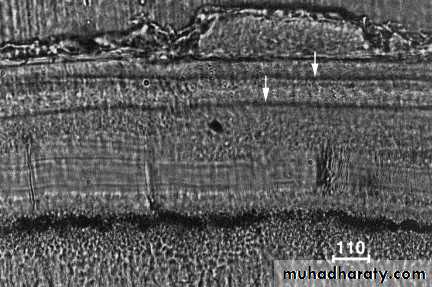

Incremental lines (also known as “resting” lines; they are produced by continuous but phasic, deposition of cementum)

Incremental lines

Under the light microscope alternating light and dark lines are visible in ground sections of human root cementum. These lines are believed to be incremental lines and to repeat at an annual rhythm. With different microscopical techniques we examine the ultra structural nature of this light microscopical phenomenon and the distribution of these lines in the rootDifferences between cementum and bone